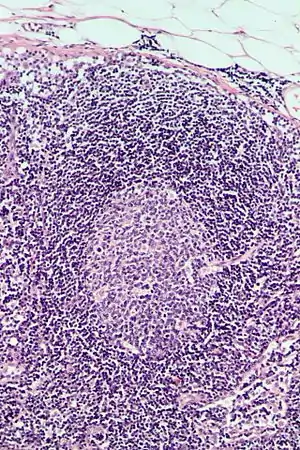

Follicular hyperplasia

Follicular hyperplasia (FH) is a type of lymphoid hyperplasia and is classified as a lymphadenopathy, which means a disease of the lymph nodes. It is caused by a stimulation of the B cell compartment and by abnormal cell growth of secondary follicles. This typically occurs in the cortex without disrupting the lymph node capsule.[1] The follicles are pathologically polymorphous, are often contrasting and varying in size and shape.[2] Follicular hyperplasia is distinguished from follicular lymphoma in its polyclonality and lack of bcl-2 protein expression, whereas follicular lymphoma is monoclonal, and expresses bcl-2.[3]

Follicular hyperplasia can be distinguished among other diseases by observing the density of a lymph follicle on low magnification. Lymph nodes with reactive follicles contain extensions outside its capsule, follicles present throughout the entire node, obvious centroblasts and the absence or diminishing mantle zones. Immunohistochemistry can help distinguish a difference between a patient with follicular lymphoma to follicular hyperplasia.[1] Reactive follicular hyperplasia does not express BCL2 proteins in B cell germinal centers and are absent light chain reaction in immunostaining and flow cytometry as well as absent IG rearrangements.[1]

BCL2 protein expression is usually absent in follicular hyperplasia but prominent in follicular lymphomas. A comparison with other stains that include germinal center markers such as BCL-6 or CD10 is useful to compare when determining a proper diagnosis.[1] CD10 positive cells are metalloproteinase which activate or deactivate peptides through proteolytic cleavage.[10]